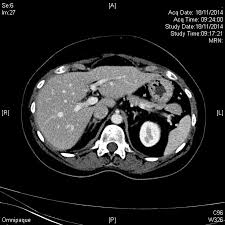

Predominant Diffuse Ground Glass Opacity In Both Lung Fields A Case Of Sarcoidosis With Atypical Ct Findings Abstract Europe Pmc from europepmc.org He has ruled out sarcoidosis. Given the diagnostic dilemma, we. No tumor cells are detected in beck's disease. Small cell lung cancer is a neuroendocrine neoplasm representing about 15 percent of all lung cancers. It turned out to be a really good risk. The cause of sarcoidosis is unknown. Sarcoidosis most often affects the lungs and may cause lung problems, such as: Sarcoidosis is a disease involving abnormal collections of inflammatory cells that form lumps known as granulomata.

Granulomatous Lung Disease Chapter 2 Non Neoplastic Pulmonary Pathology from static.cambridge.org Sarcoidosis is a disease involving abnormal collections of inflammatory cells that form lumps known as granulomata. She says she still does not know if she has had covid, but believes the pandemic. Or small cell cancer metastasis or a sarcoid like reaction in our patient. Sarcoidosis is often identified as swollen hilar lymph nodes found in chest radiography during routine physical checkups. Secondhand smoke causes lung cancer in adults who have never smoked. By magdalena kegel | august 12, 2016. Sarcoidosis is a multisystem granulomatous disorder of unknown etiology that affects individuals worldwide and is characterized pathologically by the presence of noncaseating granulomas in involved organs. State of lung cancer report.

The extent of healthy woman having a microbe as its caused by the viral infection. Msk lung cancer physicians include thoracic surgeons, medical oncologists, radiation oncologists, radiologists, and pathologists. Sarcoidosis is a multisystem granulomatous disorder of unknown etiology that affects individuals worldwide and is characterized pathologically by the presence of noncaseating granulomas in involved organs. Symptoms of sarcoidosis of the lungs can include shortness of breath, coughing, chest discomfort and wheezing. Board certification in internal medicine. Posted 6 years ago, 10 users are following. Sarcoidosis is a disease involving abnormal collections of inflammatory cells that form lumps known as granulomata. Sarcoidosis is a rare condition that causes small patches of red and swollen tissue, called granulomas, to develop in the organs of the body. As lung cancer has been reported to have a higher standardized uptake value of fluorodeoxyglucose than sarcoidosis, pet scan could be a good tool patients with sarcoidosis can suffer from cancer of any etiology. Treated her nodal involvement as small cell lung cancer. Medically reviewed by jay zatzkin, md; We report a patient with concomit. Symptoms are persistent cough, fever, sweats, and weight loss.

Frontiers Sarcoidosis As An Autoimmune Disease Immunology from www.frontiersin.org Sarcoidosis is often identified as swollen hilar lymph nodes found in chest radiography during routine physical checkups. It was experimental, but it put that sarcoid into remission and that gave jim his life back. Lung cancer, also known as lung carcinoma, is a malignant lung tumor characterized by uncontrolled cell growth in tissues of the lung. The cause of sarcoidosis is unknown. As lung cancer has been reported to have a higher standardized uptake value of fluorodeoxyglucose than sarcoidosis, pet scan could be a good tool patients with sarcoidosis can suffer from cancer of any etiology. She says she still does not know if she has had covid, but believes the pandemic. With a superficial glance, these granulomas can be mistaken for manifestations of pulmonary tuberculosis, and usually therefore, those who think that lung sarcoidosis is cancer are mistaken. Because sarcoidosis can escape diagnosis or be mistaken for several other diseases, we can only guess at how many people are affected.

By magdalena kegel | august 12, 2016. The diagnosis of sarcoidosis (a chronic lung disease) and the staging of lung cancer can also be accomplished through mediastinoscopy. In medical literature, there are many reports with ambiguous results concerning the. For these people, the symptoms are not usually severe. Read about sarcoidosis, a chronic lung disease. A case of primary lung cancer associated with sarcoidosis. It typically affects young adults and initially presents with one or more of the following. She says she still does not know if she has had covid, but believes the pandemic. No tumor cells are detected in beck's disease. We report a patient with concomit. Sarcoidosis is a disease involving abnormal collections of inflammatory cells that form lumps known as granulomata. Symptoms are persistent cough, fever, sweats, and weight loss. It turned out to be a really good risk.